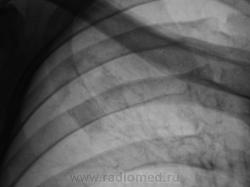

Пациент, после прохождения профилактической флюорографии "взят на контроль".  Произведено дообследование.

Я бы остановилась на множественных туберкулемах s1-2 обоих легких,Туберкулемы не однородны.за счет уплотнения,пл очаги.фиброз.

Слева туберкулома и корень подтянут Справа-очаги отсева .Динамика типичная- лечим.лечим-а туберкуломе хоть бы хны!

Туберкулёма только в С1+2 слева, как дела давно минувших дней.  Произошла реактивация туберкулёзного процесса с развитием двустороннего очагового туберкулёза. Имеется положительная динамика в виду некоторого уплотнения очагов. Таково мое мнение.